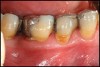

Inflammation limited to soft tissues around a dental implant may result from dental plaque colonization and is termed peri-implant mucositis. This is a reversible inflammatory condition limited to the soft tissues around the implant (without any bone loss), analogous to gingivitis around natural teeth. A diagnosis of peri-implantitis results when the inflammation spreads apically, causing progressive loss of osseointegrated supporting bone, analogous to periodontitis around natural teeth16 (Figure 2A and Figure 2B). It is essential for practitioners to be familiar with these diagnostic terms when assessing the long-term success of implants and peri-implant health (Table 1).

Figure 2a

Figureb 2  (A) Clinical and (B) radiographic views of implants at site Nos. 30 and 31 demonstrating bone loss caused by peri-implantitis after 8 years in function. Note gingival inflammation and plaque accumulation around implants.

Figure 2b